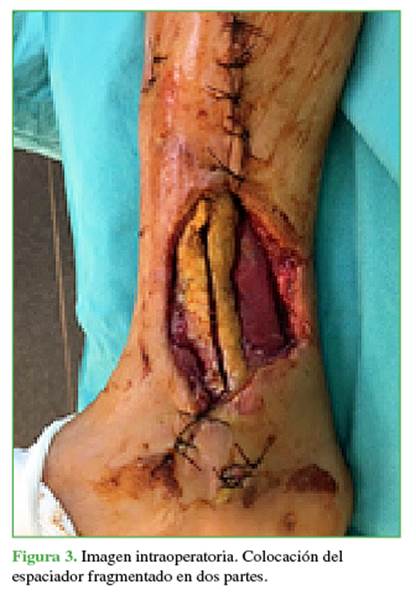

Estabilización ósea con clavo intramedular cubierto con cemento impregnado de antibióticos. Cobertura de partes blandas. En todos los casos, el tercer espacio muerto generado por la resección ósea fue manejado usando un espaciador circunferencial de cemento impregnado de antibióticos fragmentado en dos hemicilindros a fin de facilitar su extracción (Figura 3).